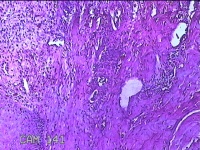

右侧食指远端结节

性别

男

年龄

47岁

临床诊断

皮下结节

一般病史

发现右侧食指3天。

标本名称

大体所见

灰白暗红色带皮肤样结节1.2x0.7x0.3cm一个,表面糜烂,切面灰白粉红色,质中。

应该是个良性病变,建议把主要病变区域来个地倍高倍,现在拍的炎症、溃疡的地方比较多